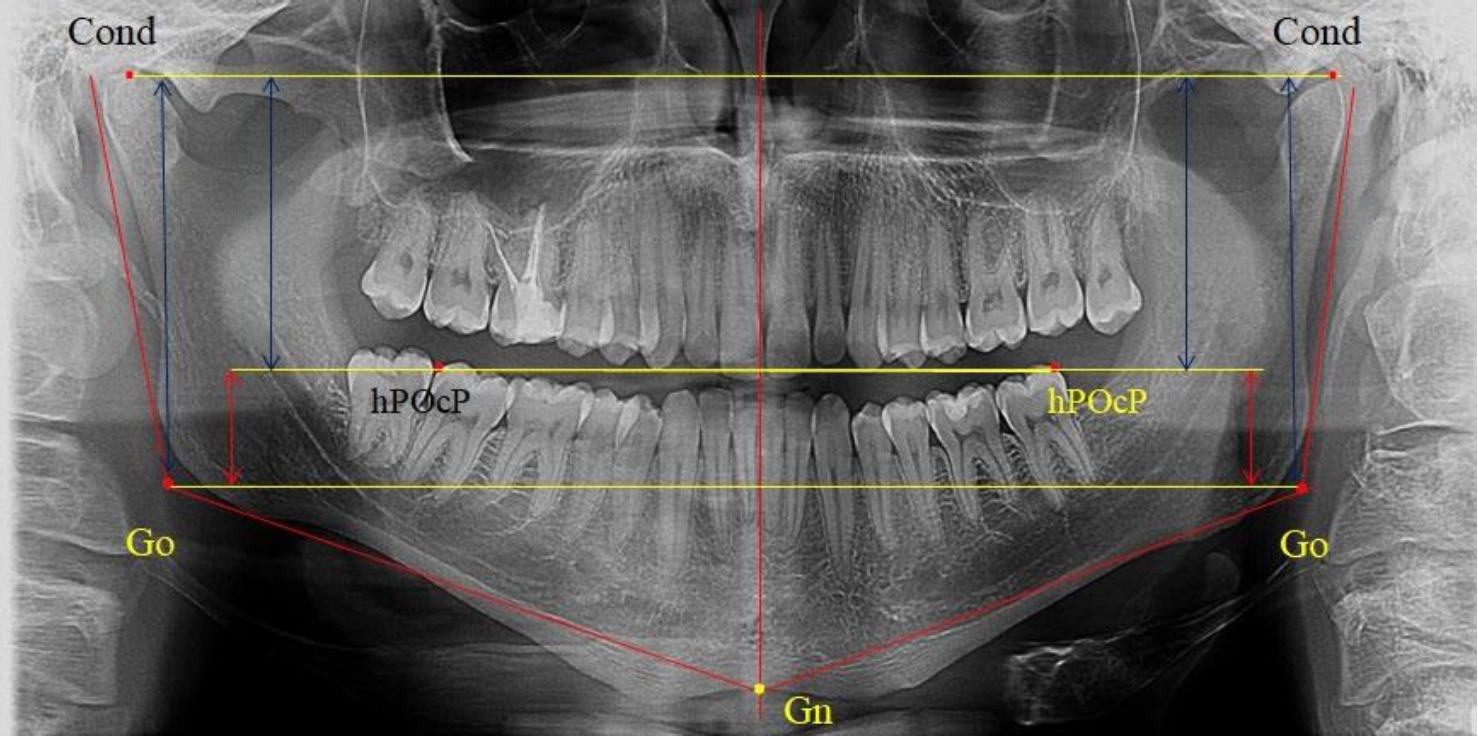

3-я подгруппа была с наименьшим количеством анализируемого материала, и здесь было проанализировано 17 комплектов рентгенограмм [(22,97 ± 4,89) %], на которых средняя величина отношения верхней части ветви к нижней составляла 2,45 ± 0,04, что было достоверно больше показателя, полученного по группе в среднем, а также в 1-й и 2-й подгруппе. Визуально параметры ветви отличались от других подгрупп. Высота ветви составляла (57,83 ± 0,89) мм, что было несколько меньше, чем в других подгруппах. Максимальная высота была 64 мм, а минимальная – 53 мм. Высота верхней части составляла (41,03 ± 0,59) мм, что было близким по значениям, полученным в других подгруппах и свидетельствовало о меньшей вариабельности указанного параметра. В то же время высота нижнего отдела ветви была (16,83 ± 0,36) мм и показатель отличался в меньшую сторону, по сравнению с аналогичным размеров в других подгруппах (рис. 4).

Рис. 4. ОПТГ пациента 3-й группы с увеличенным коэффициентом соотношения частей ветви нижней челюсти